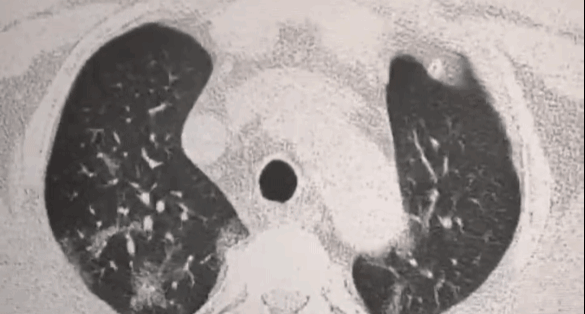

受损的肺细胞会形成肺结节

进而引发肺部纤维化、甚至肺ai

医学上对肺结节没有特效药

一般只能手术切除

对肺部的伤害大,有副作用

没有清理肺部的自由基

治标不治本,肺结节容易二次复发

肺部有很多结节

张女士于2021年11月份检查出4.2MM左肺混合磨现璃结节,右肺3.8MM纯磨玻璃结节。

服用4瓶美国TTU槲皮素周期,复查发现结节已经完全消除。无明显异常,不咳嗽了痰也变少了。